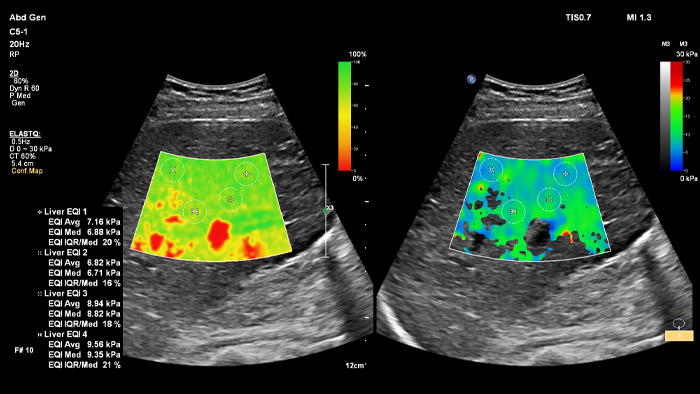

ElastQ bietet mit der 2D-Scherwellen-Elastographie (2D-SWE) eine nichtinvasive, reproduzierbare und einfach durchzuführende Echtzeit-Beurteilung der Gewebesteifigkeit. Außerdem beinhaltet ElastQ Imaging eine Funktion zur retrospektiven Messung an gespeicherten Bildern sowie eine entsprechende Darstellung der statistischen Sicherheit für die höchste Scherwellenausbreitung.

ElastQ Imaging